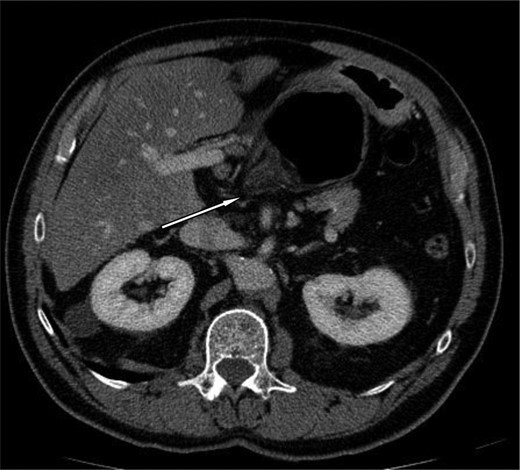

A 69-year-old patient presented to our emergency room with progressive dull abdominal pain and distension without nausea, vomiting or change in bowel habits. Physical examination showed pain with moderate guarding in the right upper and lower quadrants. A plain abdominal X-ray and a CT scan were performed. Radiological findings suggested the diagnosis of an internal hernia through the epiploic foramen and containing the right colon with important distension of the caecum (Fig. 1). Surgical exploration was then performed using an open approach. At laparotomy, we found an internal herniation of the caecum and the entire ascending colon through the foramen of Winslow (Figs 2 and 3). After hernia reduction, multiple patchy areas of caecal necrosis were observed (Fig. 4). A formal right hemi-colectomy was therefore performed. The postoperative recovery was uneventful.

Coronal slice showing herniation of right colon through the foramen of Winslow.